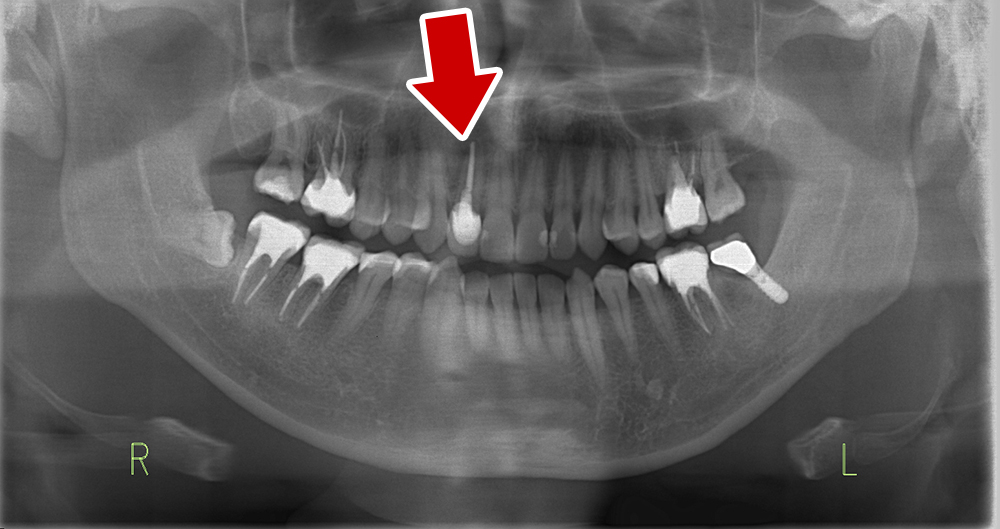

45歳 男性 医療関係者紹介

- 主訴

- 右前歯が取れた(右上2)

- 処置内容

-

1本インプラント埋入+再生療法

抜歯即時埋入⇒抜歯を行い、同時にインプラント埋入(即時埋入)

- 治療費用

- 上顎:約40万円(税込)

- 治療期間

- 約11か月

- リスク

- 上部構造物、仮歯の破折、術後の腫れ(3日)、人工歯根脱落リスクがあります